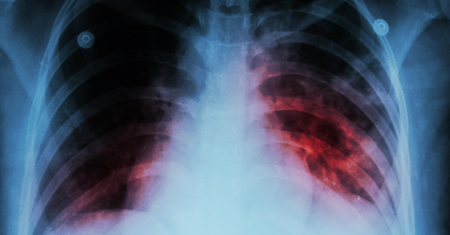

Tuberculosis

Accurate diagnosis and complete treatment of pulmonary and extrapulmonary tuberculosis with guideline-based care.